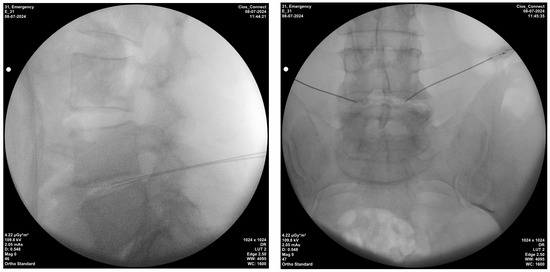

Bipolar radiofrequency thermocoagulation was performed in a sterile room. Sedation was administered to all monitored patients beforehand. Patients placed in the prone position had their treatment area cleaned and covered with a sterile drape, the disc level and entry point where the interventional procedure was performed were localized using C-arm fluoroscopy with the tunnel vision technique. Appropriate disc level and needle placement were confirmed with a posteroanterior fluoroscopic view and advanced, whereas depth was confirmed with a lateral fluoroscopic view (Figure 2). After the procedure, a mixture of 1 mL physiological saline solution and an antibiotic (cephalosporin) was injected into the disc, and the procedure was completed. A 20-gauge, 15 cm needle, and 10 mm active-tip catheter were inserted into the disc. Following a lack of response (no sensory or motor response) to 2 Hz and 50 Hz at 2 V, a lesion was consecutively created at 50 °C for 2 min, 55 °C for 2 min, 60 °C for 2 min, and 65 °C for 4 min using an NT1100 RF generator (NeuroTherm, Middleton, MA, USA) [19].

Figure 2. Techniques of intradiscal bipolar radiofrequency thermocoagulation injection; lateral and posterior–anterior fluoroscopic views.